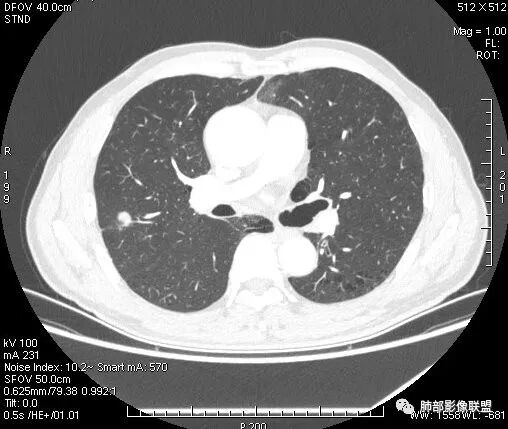

影像学改变:

1.右肺上叶后段类圆形结节影,密度不均,有坏死空洞,坏死比较彻底,内外壁都较清楚。

2.病灶有浅切迹,没有深分叶,毛刺大多细长且柔软。

3.可见棘状突起及胸膜牵拉,但未见胸膜凹陷。

什么意思?结节影有牵拉的动作,但似乎“出工不出力”,收缩力羸弱!

4.病灶轻到中度强化。病灶内血管走行较完好,病灶旁血管局部显示粗大。

5.支气管关系不确定。

6.灶周见小结节影(卫星灶),边界不甚清晰。